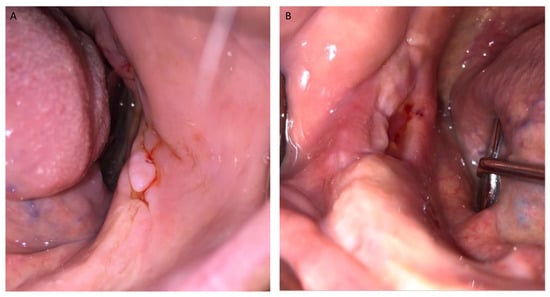

Figure 6.

(A,B) Post-operative intra-oral view at 2 week follow-up. Mucosal healing without bone exposure can be seen.

Figure 7.

(A,B) Post-operative intra-oral and radiographic view at 6 month follow-up showing healed soft (A) and hard (B) tissues.